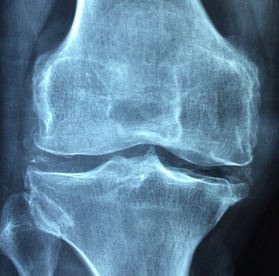

무릎이 아프면 아무것도 못하죠. 제가 무릎통증 원인을 알려드릴께요

무릎통증 원인

무릎통증은 반복된 스트레스가 주요 원인인데요. 잘못된 자세를 반복하는 것이 문제가 되요. 계단을 내려가는 동작이 안좋다고 합니다. 하지만 계단을 오르는 것은 좋다고 하네요. 허벅지 근육이 움직이는 거래요.

그리고 운동을 하다가 다치는 경우도 있는데요. 축구 같이 방향전환을 하는 경우가 많잖아요. 그러면 다칠확률이 높아요.제 아는 지인도 축구를 하다가 그만 무릎이 아작이 난경우가 있어요. 그래서 수술을 했는데 결과가 좋지는 않더라구요. 무엇보다 예방이 중요하죠